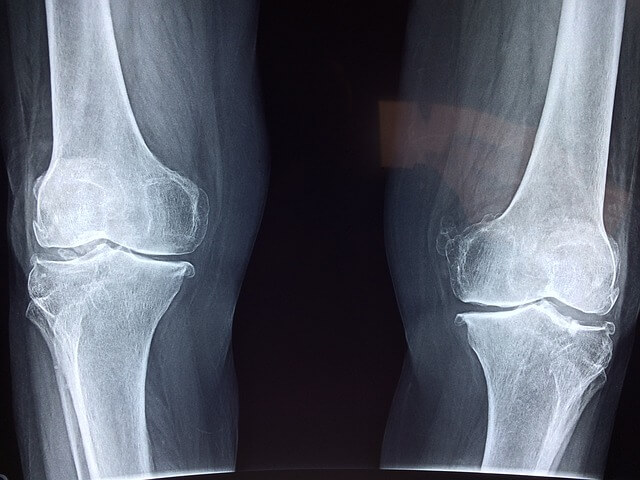

무릎이 아픈 것은 무릎 연골이 닳아서 아프다고 잘못 아시고 계신분이 있는데, 사실 연골에는 신경세포가 없으며, 통증 자체는 염증이 생긴 활막이 자극을 받아서 활막을 통해서 통증을 느끼는 것입니다.

뼈 들이 만나는 지점인 관절에서 발생하는 질환입니다.

가장 일반적인 것이 퇴행성 관절염 (골 관절염)으로 뼈 끝을 감싼 연골이 닳아 통증과 부종이 일으키는 것입니다. 노화 관절에 생기는 상처나 감염 등이 원인이 되어 발생합니다.